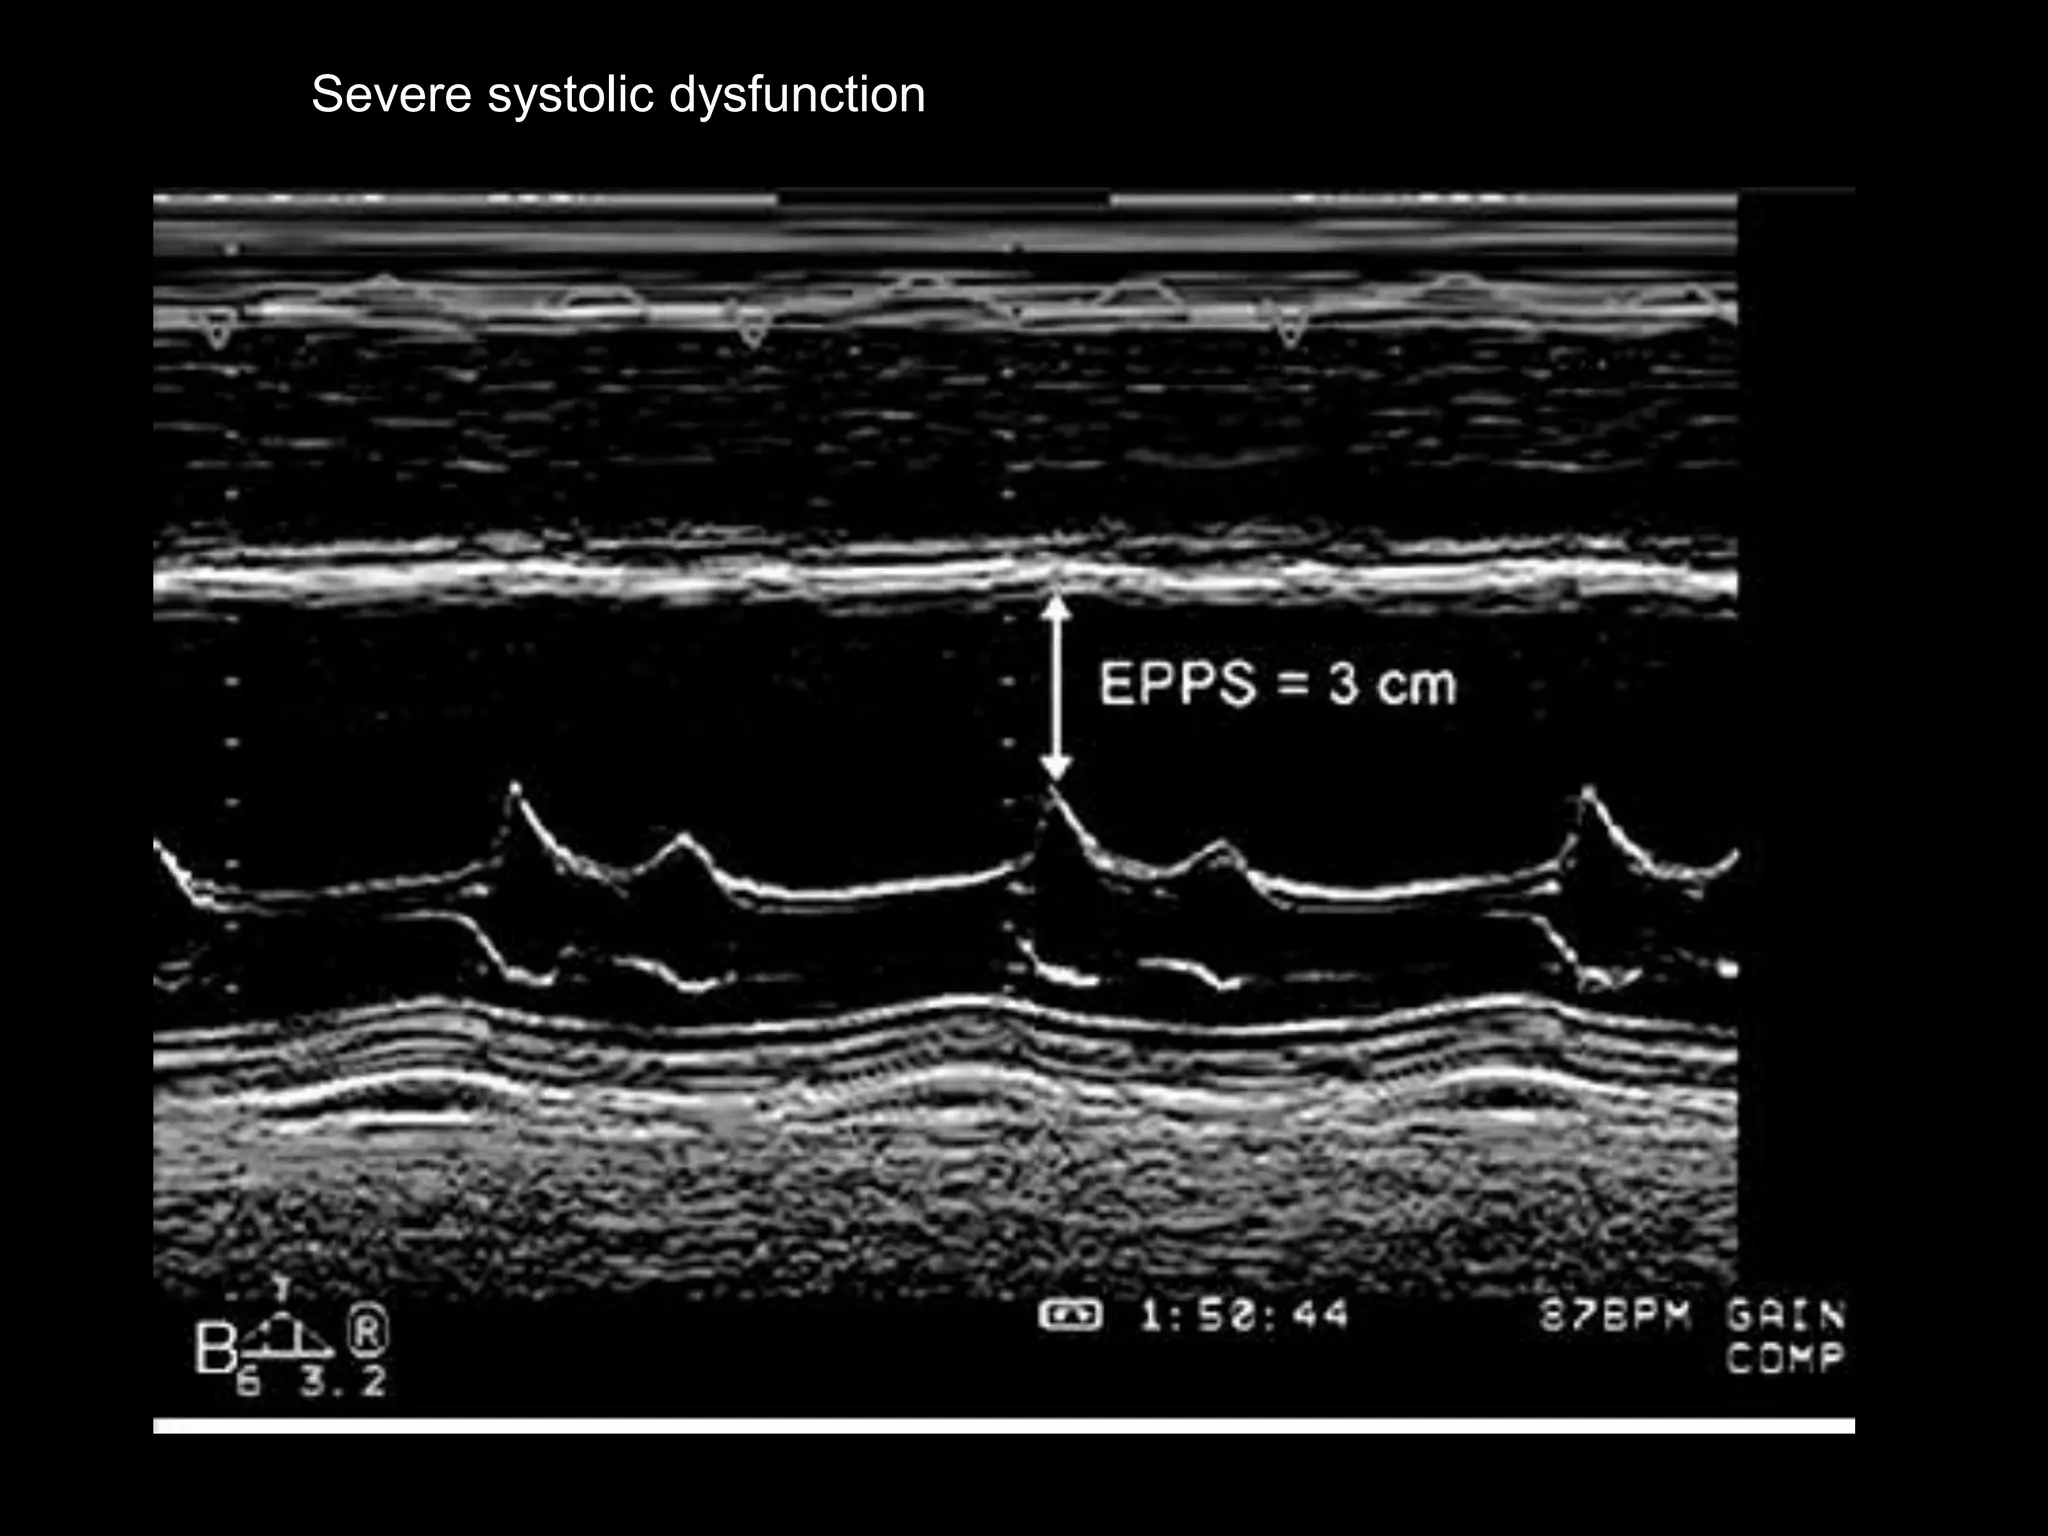

1. E-point septal separation

 magnitude of opening of the mitral valve=E-

wave height, correlates with transmitral flow

and, in the absence of significant MR, with LV

SV

 Mitral valve E point (maximal early opening) -

within 6 mm of the left side of the ventricular

septum

 decreased ejection fraction-distance is

increased

Severe systolic dysfunction